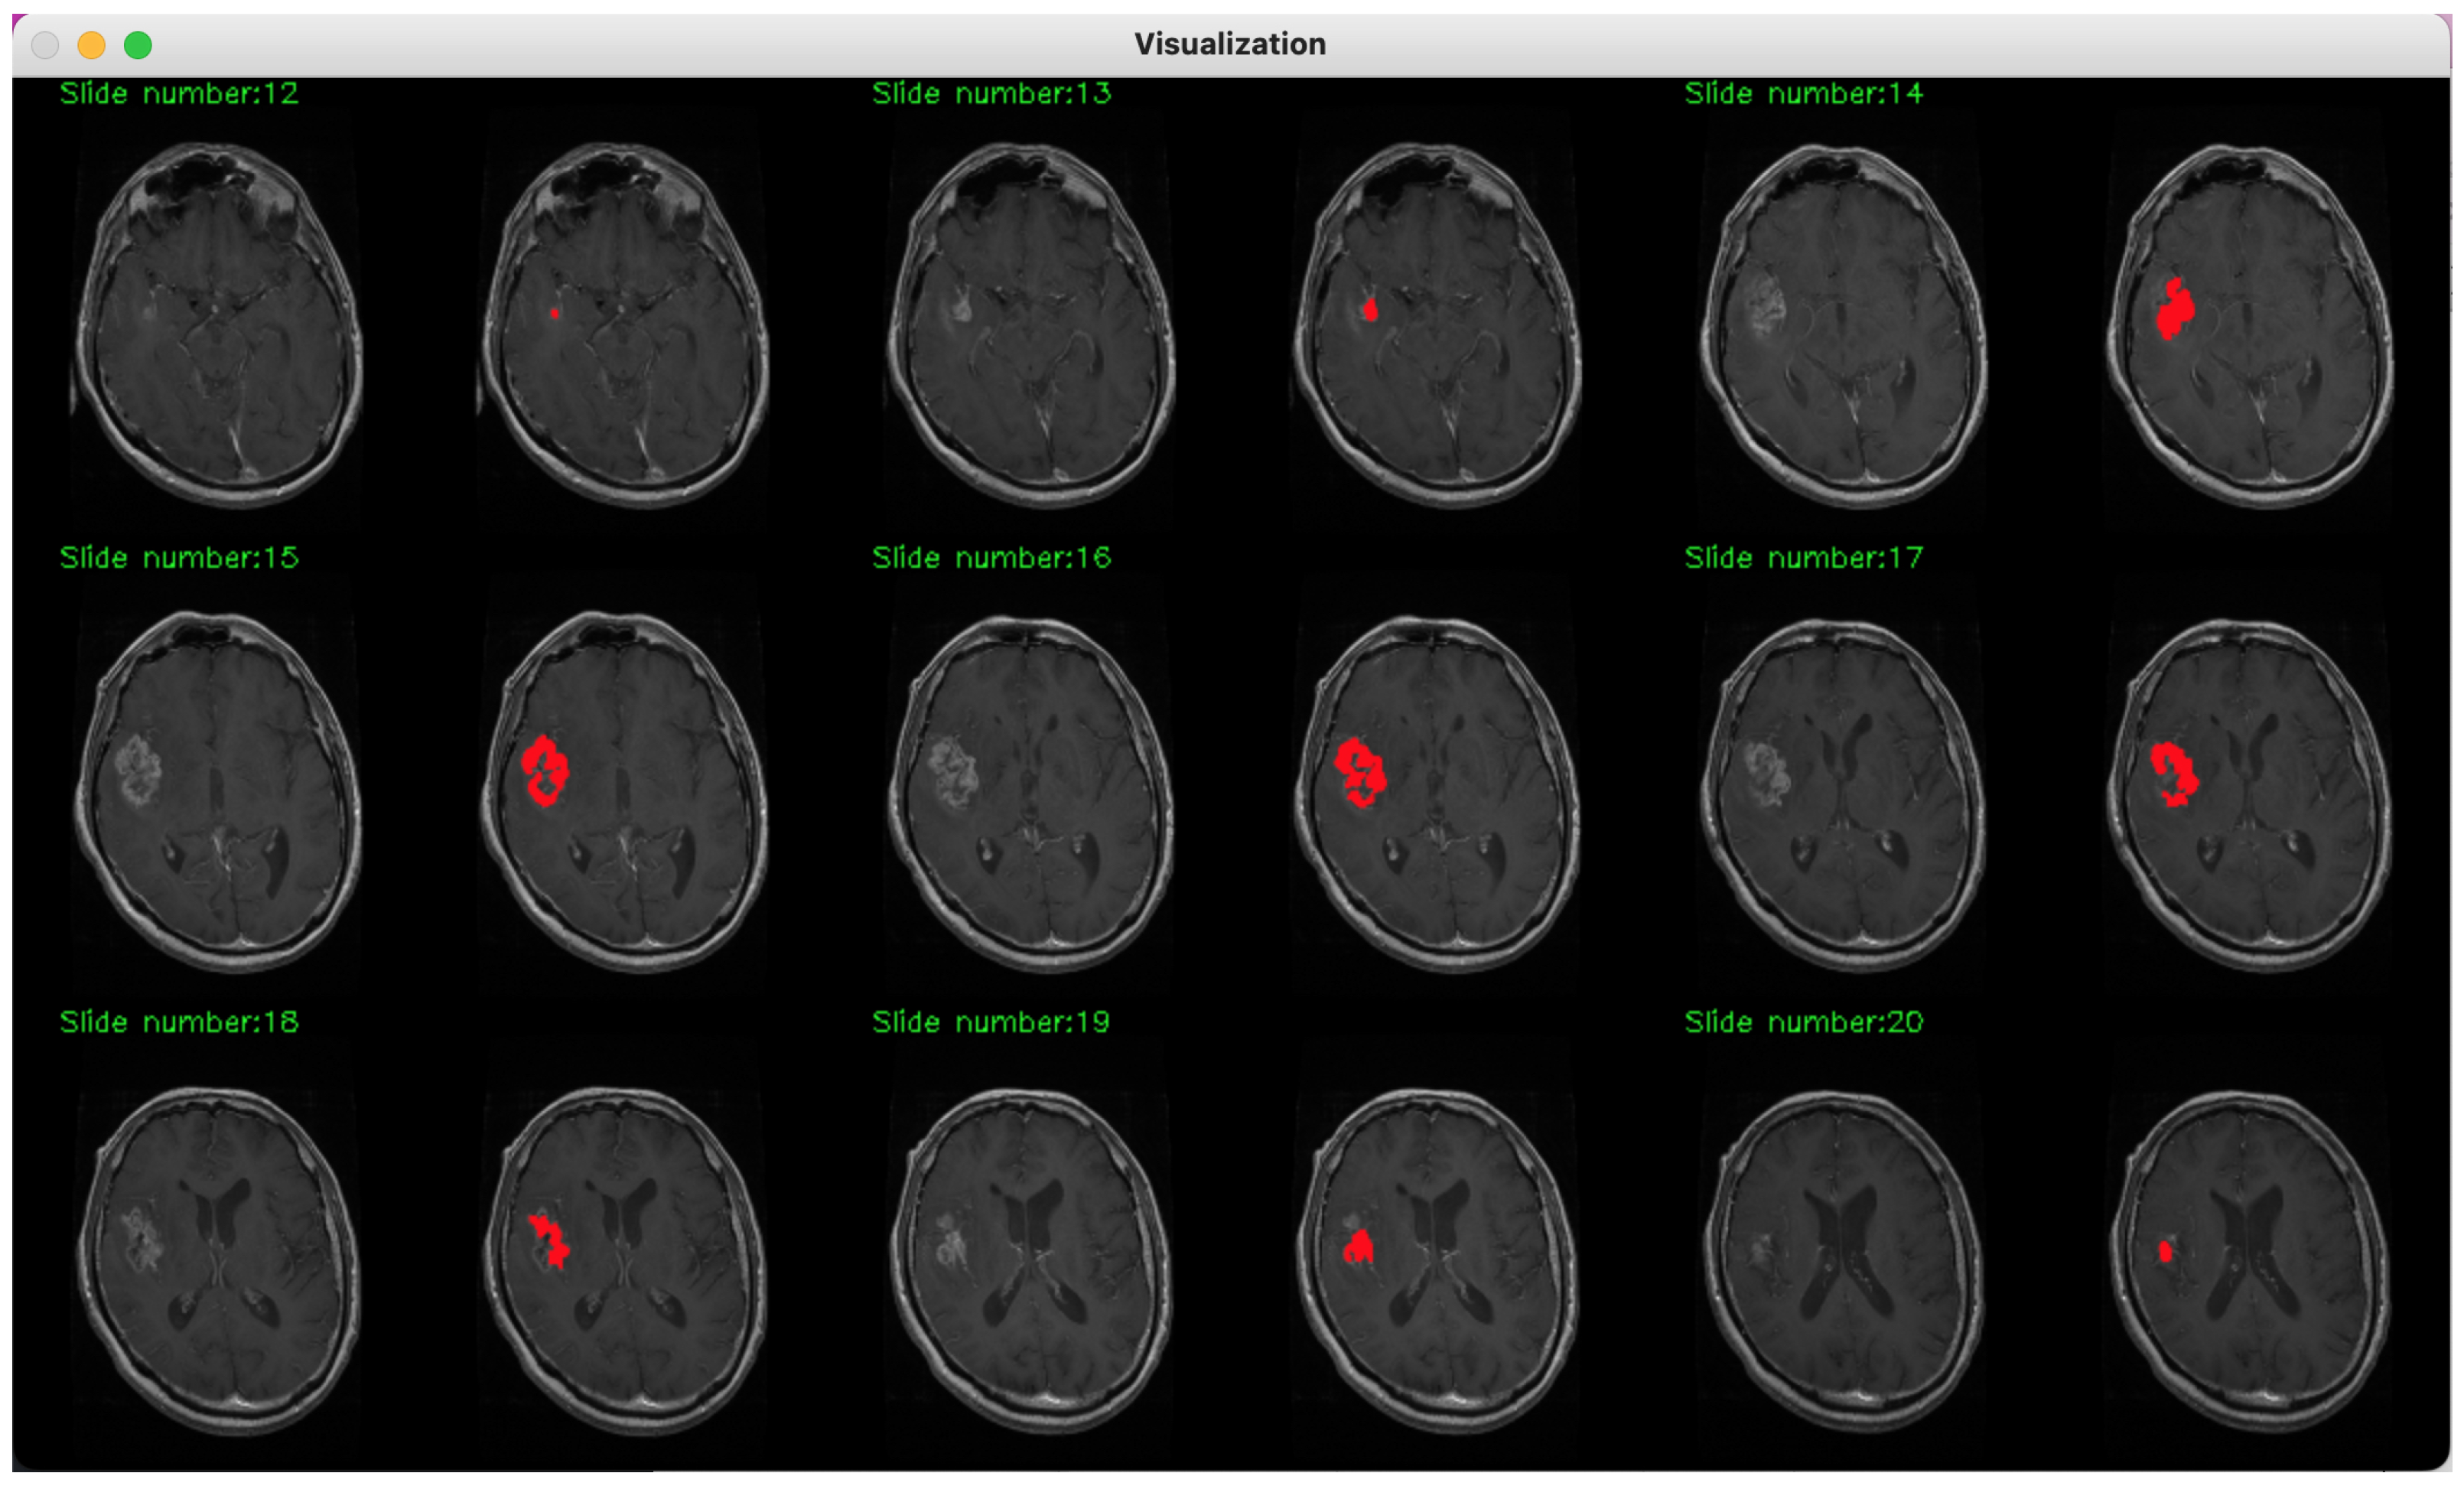

2. Method Description